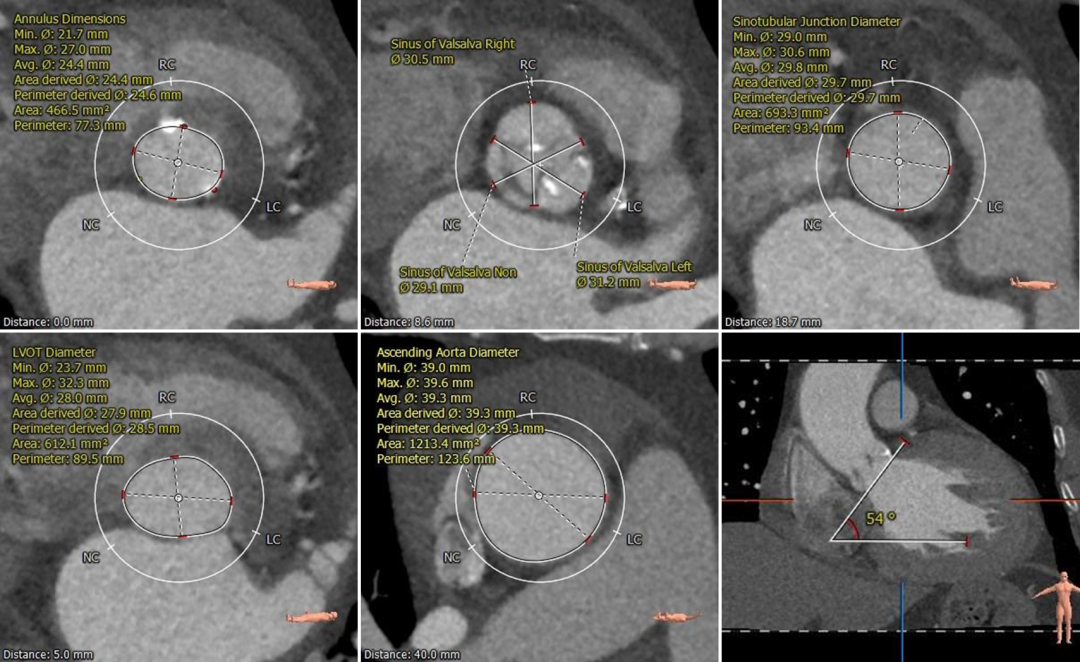

术前CT评估

• 三叶式主动脉瓣,中度钙化,主要分布于左右窦窦底并延伸到瓣环-流出道水平,无冠窦发育畸形,窦内空间小;

• 双侧冠脉开口高度可,切线角度测量,左窦瓣叶略长于左冠开口到瓣叶根部距离;

• 无冠窦内径略小,左右窦内径可,窦管交界、升主动脉内径可;

• 非横位心,主动脉弓宽度角度可;

• 主动脉、双侧股髂血管内径及走行可,未见明显钙化及狭窄。

根部测量

瓣环平均径24.6mm,STJ、升主内径可,非横位心

冠脉测量

冠脉开口高度可,切线位测量左窦瓣叶略长于左冠开口

钙化分布

中度钙化,HU 600 629mm³,HU850 182mm³

弓部及入路

弓部宽度角度可,双侧股髂动脉内径及走行可

病例特点

该病例为三窦式,无冠窦先天发育畸形,窦内空间小并存在嵴样间隔,钙化主要分布在左右窦接近窦底位置并向下延伸,左窦瓣叶略长,可疑阻挡风险,术中需加以关注。